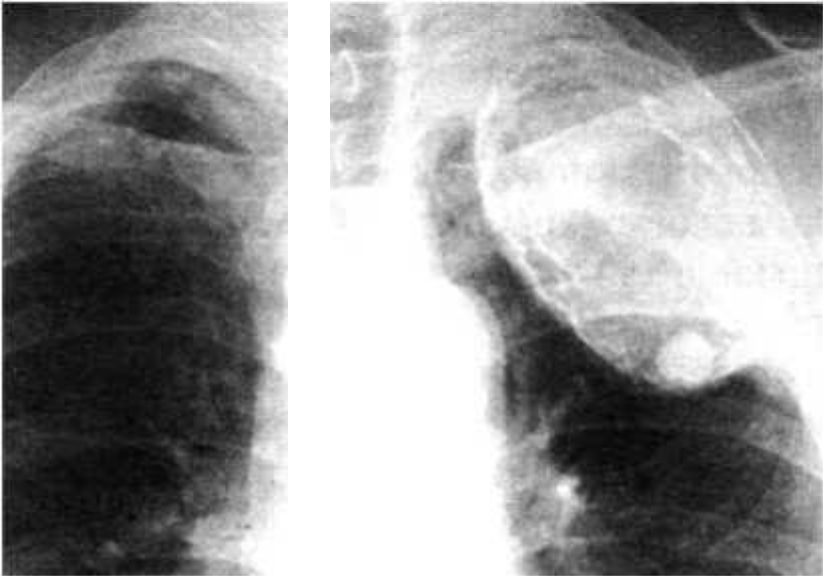

Понимание кавернозного туберкулеза почки

Раздел: Мудрость в деталях